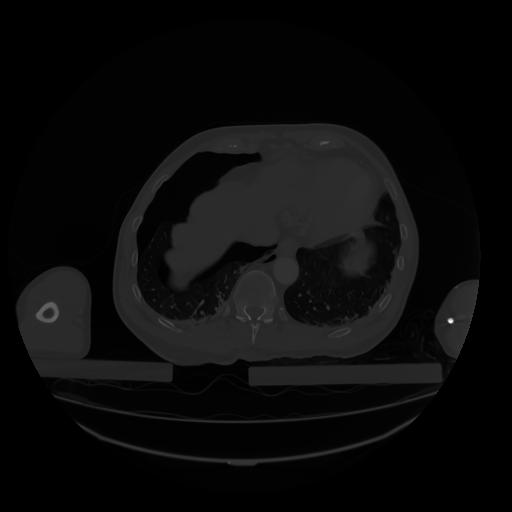

28 CUERPO,CE,Vol,2.0,CUERPO,,